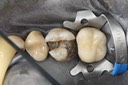

Mark Chun #14 prep